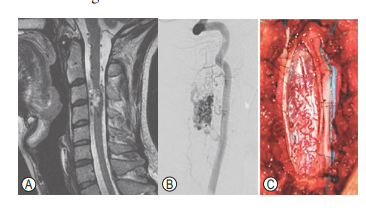

Which one of the following is most likely from

the images below?

e. Type II intramedullary (Glomus) AVM

Type II intramedullary (glomus) AVMs are characterized by a compact intramedullary nidus, with feeding vessels arising from the anterior or posterior spinal arteries, or both, and drainage into an arterialized coronal venous plexus. Unlike spinal AV fistulas they are high pressure, low-flow lesions (rapid filling on angiogram and early venous drainage).

Affect men and women equally, and mean age of

presentation in 20s. The clinical course of these

lesions is marked by progressive and fluctuating

myelopathy, often overlaid by periods of acute neurologic deterioration secondary to hemorrhage

within the AVM. Sudden apoplectic presentation,

often with profound neurologic impairment and

possible transverse myelopathy is common. SAH

often occurs in these lesions, occurring in 50% of

cases.TrueintramedullaryAVMs occur throughout

the cord hence presentation with upper extremity

symptoms is possible. Imaging demonstrates intramedullary AVM at C3-C4 levels with associated

hematoma and flow voids from arterialized coronal venous plexus of the spinal cord, while angiogram

demonstrates feeders arising from the left vertebral artery. Treatment involves initial embolization of feeding vessels using particulate matter. Immediate clinical improvement is often noted after embolization, through reduction in arterial steal and improved cord perfusion; however, recanalization may occur over time, with continued risk of hemorrhage. Hence, surgical resection of residual nidu after embolization is generally reasonable.